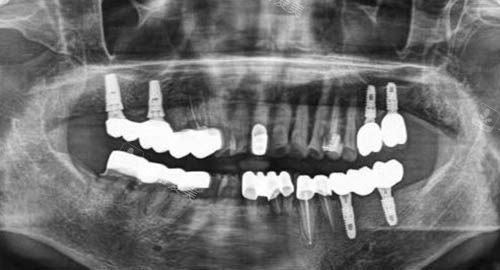

多颗牙齿种植ct

在种植前,医院会为患者进行齐全的口腔检查,包括口腔 CT 扫描等。

通过这些检查,医生能够获取患者口腔的详细数据,如牙槽骨的密度、高度、宽度等。

然后,利用智能化种植系统对这些数据进行分析和处理,制定出个性化的种植方案。

该系统能够模拟种植过程,精细计算出种植体的植入位置、角度和深度,确保种植体能够较准地植入到更佳位置。